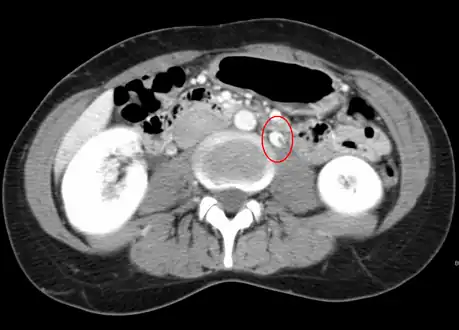

Left kidney with a suprarenal anechoic cyst-like lesion and hyperechoic intermedullary streaks in initial phase of renal vein thrombosis -

CT showing dilatation and thrombosis of the left renal vein in a patient with nutcracker syndrome

Observing the patient's symptoms, medical history and imaging remain the fundamental source for diagnosing RVT. Imaging is used to detect the presence of a blood clot. In an abnormal kidney with RVT, a blood clot is present in the renal vein. In cases where the renal vein is suddenly and/or fully blocked, the kidneys will enlarge, reaching its maximum size within a week. An ultrasound imaging can be used to observe and track the size of the kidneys in RVT patients. Ultrasound is not efficient for use in detecting blood flow in the renal veins and artery. Instead a color doppler ultrasound may be used to detect renal blood flow. It is most commonly used to detect RVT in patients who have undergone renal transplantation. CT angiography is currently the top choice in diagnosing RVT. It is non-invasive, relatively cheap and fast with high accuracy. CT scanning can be used to detect renal enlargement, renal tumors, blood flow and other renal pathologies. An alternative is magnetic resonance angiography or MRA. It is non-invasive, fast and avoids radiation (unlike a CT scan) but it is relatively expensive. MRA produces detailed images of the renal blood flow, vesicle walls, the kidneys and any surrounding tissue. An inferior venocavography with selective venography can be used to rule out the diagnoses of RVT.[6]